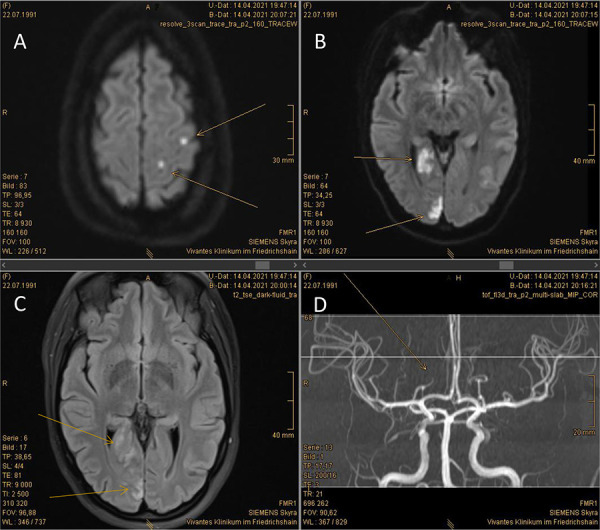

在急诊环境中,血小板减少症总是令人担忧。我们报告了一例 29 岁女性患者的病例,她出现了一系列独特的血液病。患者于 2007 年被诊断为特发性免疫性血小板减少症(ITP),并有多次血小板减少症复发的病史。现在,她出现同侧偏盲,伴有血小板减少和微血管病性溶血性贫血(MAHA),不久后被诊断为后发中风。症状更像是获得性血栓性血小板减少性紫癜(aTTP),而不是 ITP。立即进行血浆置换和卡普拉珠单抗治疗后,MAHA症状得到缓解,并避免了进展性缺血性疾病的发生。ADAMTS-13 检测确诊为免疫介导的 aTTP。然而,ITP的重复检测也显示出了IgG-负载的血小板,具有前者已知的抗GPIIb/IIIa特异性。此外,自身免疫性溶血性贫血(AIHA)可通过直接抗球蛋白试验检测到,该试验显示患者红细胞中含有 IgG 和补体。这三种病症的自身免疫背景都提示存在潜在的系统性疾病。事实上,系统性红斑狼疮(SLE)血清学检测呈强阳性,可以诊断为系统性红斑狼疮。ITP和AIHA以及aTTP可继发于系统性红斑狼疮,但同时出现这三种疾病的情况尚未见报道。

Thrombocytopenia is always of concern when encountered in emergency settings. We report a case of a 29-year-old women in whom a unique constellation of hematological disorders occurred. The patient had been diagnosed with idiopathic immune thrombocytopenia (ITP) in 2007, with a history of several thrombocytopenic flares. She now presented with homonymous hemianopia accompanied by thrombocytopenia and microangiopathic hemolytic anemia (MAHA) and was soon after diagnosed with a posterior stroke. Symptoms were more reminiscent of acquired thrombotic thrombocytopenic purpura (aTTP) rather than ITP. Immediate treatment with plasma exchange and caplacizumab curtailed MAHA, and progressive ischemic disease was averted. ADAMTS-13 testing confirmed the diagnosis of immune-mediated aTTP. Repeated testing for ITP, however, also showed IgG-loaded thrombocytes with the former known anti-GPIIb/IIIa specificity. Furthermore, autoimmune hemolytic anemia (AIHA) could be detected by direct antiglobulin test showing IgG and complement loading of the patient's erythrocytes. The autoimmune background of all three entities suggested an underlying systemic disease. Indeed, systemic lupus erythematosus (SLE) serology was strongly positive allowing for the diagnosis of SLE. ITP and AIHA as well as aTTP can be secondary to SLE, but emergence of all three disorders has not been reported at the same time.